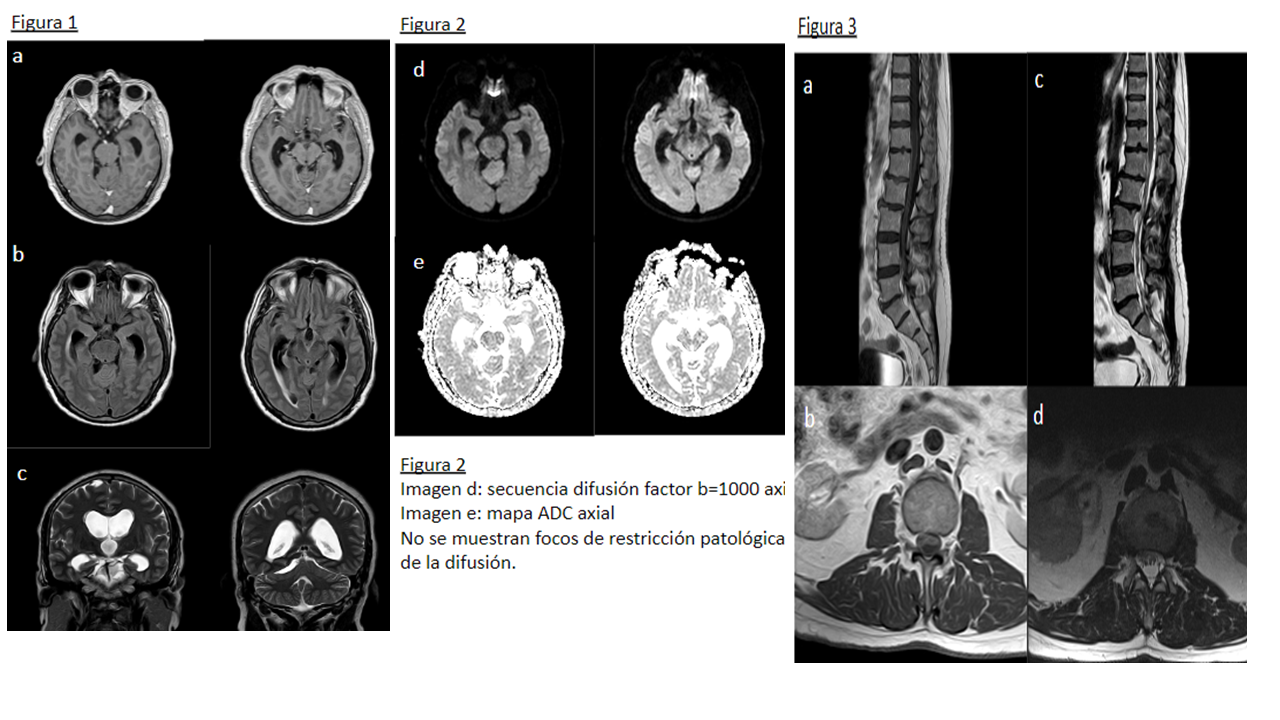

Figura 1 Imagen a: secuencia T1 con contraste axial Imagen b: secuencia FLAIR axial

Imagen c: secuencia T2 coronal Leve ampliación de cisternas de la base craneal, con algún septo, especialmente en la cisterna perimesencefálica y ambiens en el lado derecho con leve distorsión de estructuras encefálicas próximas. No existe realce leptomeníngeo tras la administración de gadolinio. En el T2 coronal se aprecia hidrocefalia supratentorial con edema transependimario y borramiento generalizado de los surcos de la convexidad hemisférica.

Figura 2 Imagen d: secuencia difusión factor b=1000 axial Imagen e: mapa ADC axial No se demuestran focos de restricción patológica de la difusión.

Figura 3 Imagen a: secuencia T1 con contraste sagital Imagen b: secuencia T1 con contraste axial Imagen c: secuencia T2 sagital Imagen d: secuencia T2 axial Las raíces de la cola de caballo se encuentran engrosadas y agrupadas en el centro del saco tecal, con distorsión de su contorno y nodularidad de la superficie, que muestra realce tras la administración de gadolinio.